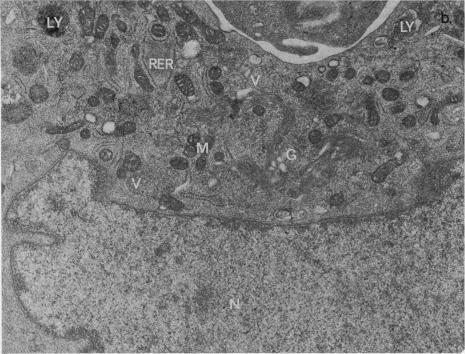

Cultures of human astrocytoma have been derived by collagenase digestion and are presumed, from their aneuploid karyotypes, to be predominantly neoplastic. Early passage cultures in proliferative phase have been cloned in the presence of dexamethasone and betamethasone, both commonly used in management of patients with brain tumours. These steroids raise both the cloning efficiency and the proliferative capacity of cells within each clone. Inhibition was detected only in very high steroid concentrations (25-50 microng/ml). Since these concentrations are unlikely to be attained in vivo it is concluded that anticipated physiological levels of these steroids enhance cell survival at low densities in culture. The significance of this in vivo is discussed.

人星形细胞瘤培养物通过胶原酶消化获得,从其非整倍体核型推测,这些培养物主要是肿瘤性的。处于增殖期的早期传代培养物已在常用治疗脑肿瘤患者的地塞米松和倍他米松存在的情况下进行克隆。这些类固醇提高了每个克隆内细胞的克隆效率和增殖能力。仅在非常高的类固醇浓度(25 - 50微克/毫升)下检测到抑制作用。由于这些浓度在体内不太可能达到,因此得出结论,这些类固醇的预期生理水平可提高培养中低密度细胞的存活率。文中讨论了其在体内的意义。